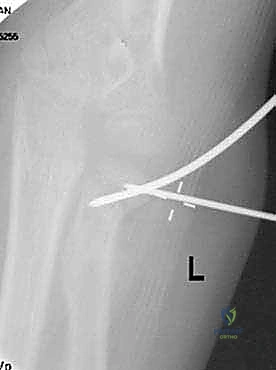

استخدام سلك معدني (K-wire) كعصا تحكم لتوجيه رأس الكعبرة المكسور بدقة متناهية.

صورة شعاعية تظهر التثبيت النهائي للكسر باستخدام الأسلاك المعدنية المتقاطعة لضمان الاستقرار التام.